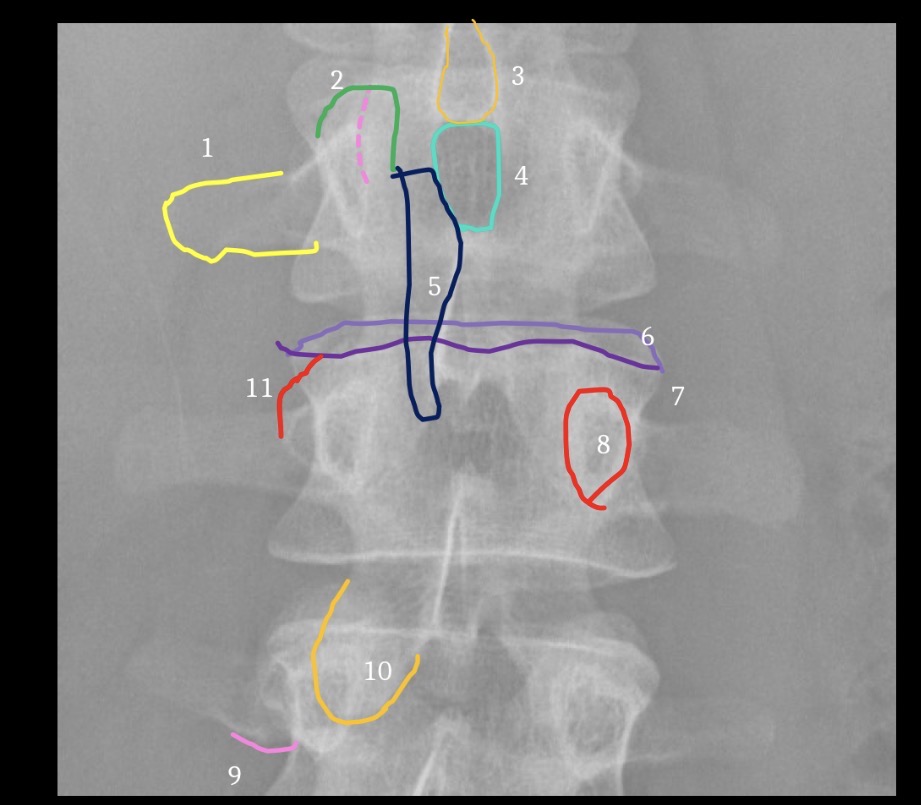

1

Inferior Margin of right 1th rib

2

Spinous process of T12

3

Left pedicle of L2

4

Left transverse process of L3

5

Right facet joint space L2-3

6

L4 spinous process

7

Inferior margin of right lamina L5

8

Right sacral ala

9

Superior margin right 1st anteror sacral foramen

10

Left margin of sacrum

11

Left iliac crest

12

Left posterior iliac spine

13

Superior margin left acetabulum

14

Gonadal shielding

15

Gas in colon

16

Inferior margin of liver